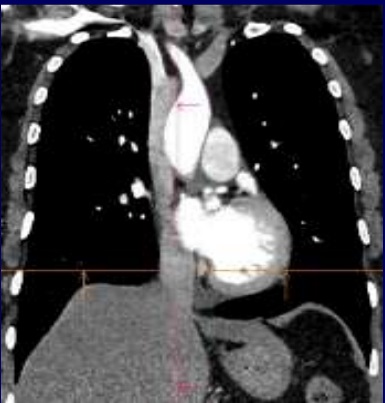

Même cas en coupe TDM coronal

, fenêtre mediastinale .

Click pour entrer |